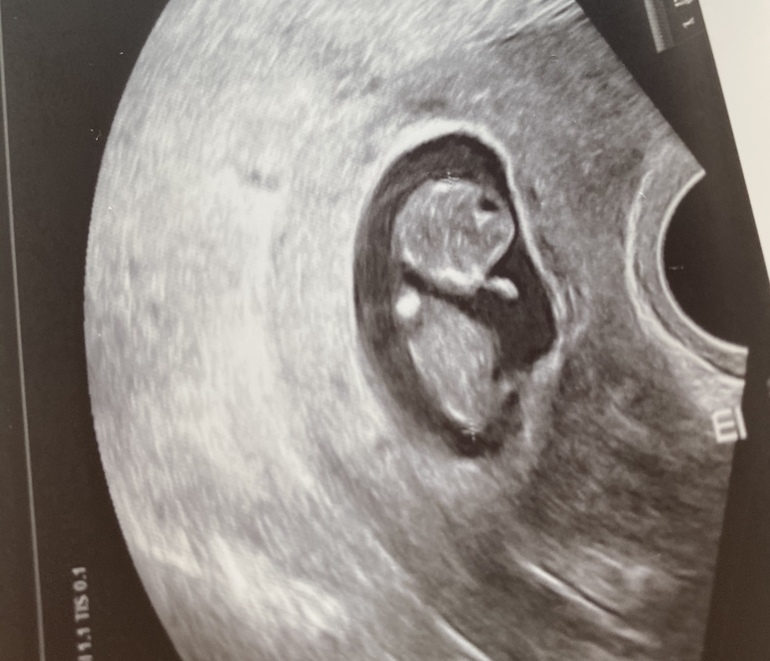

УЗИ

Ой, какой большой человек уже 👍🏻